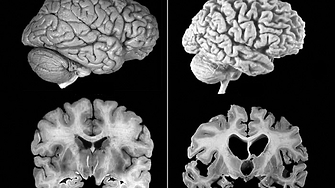

Болестта на Алцхаймер е най разпространената форма на деменция в световен